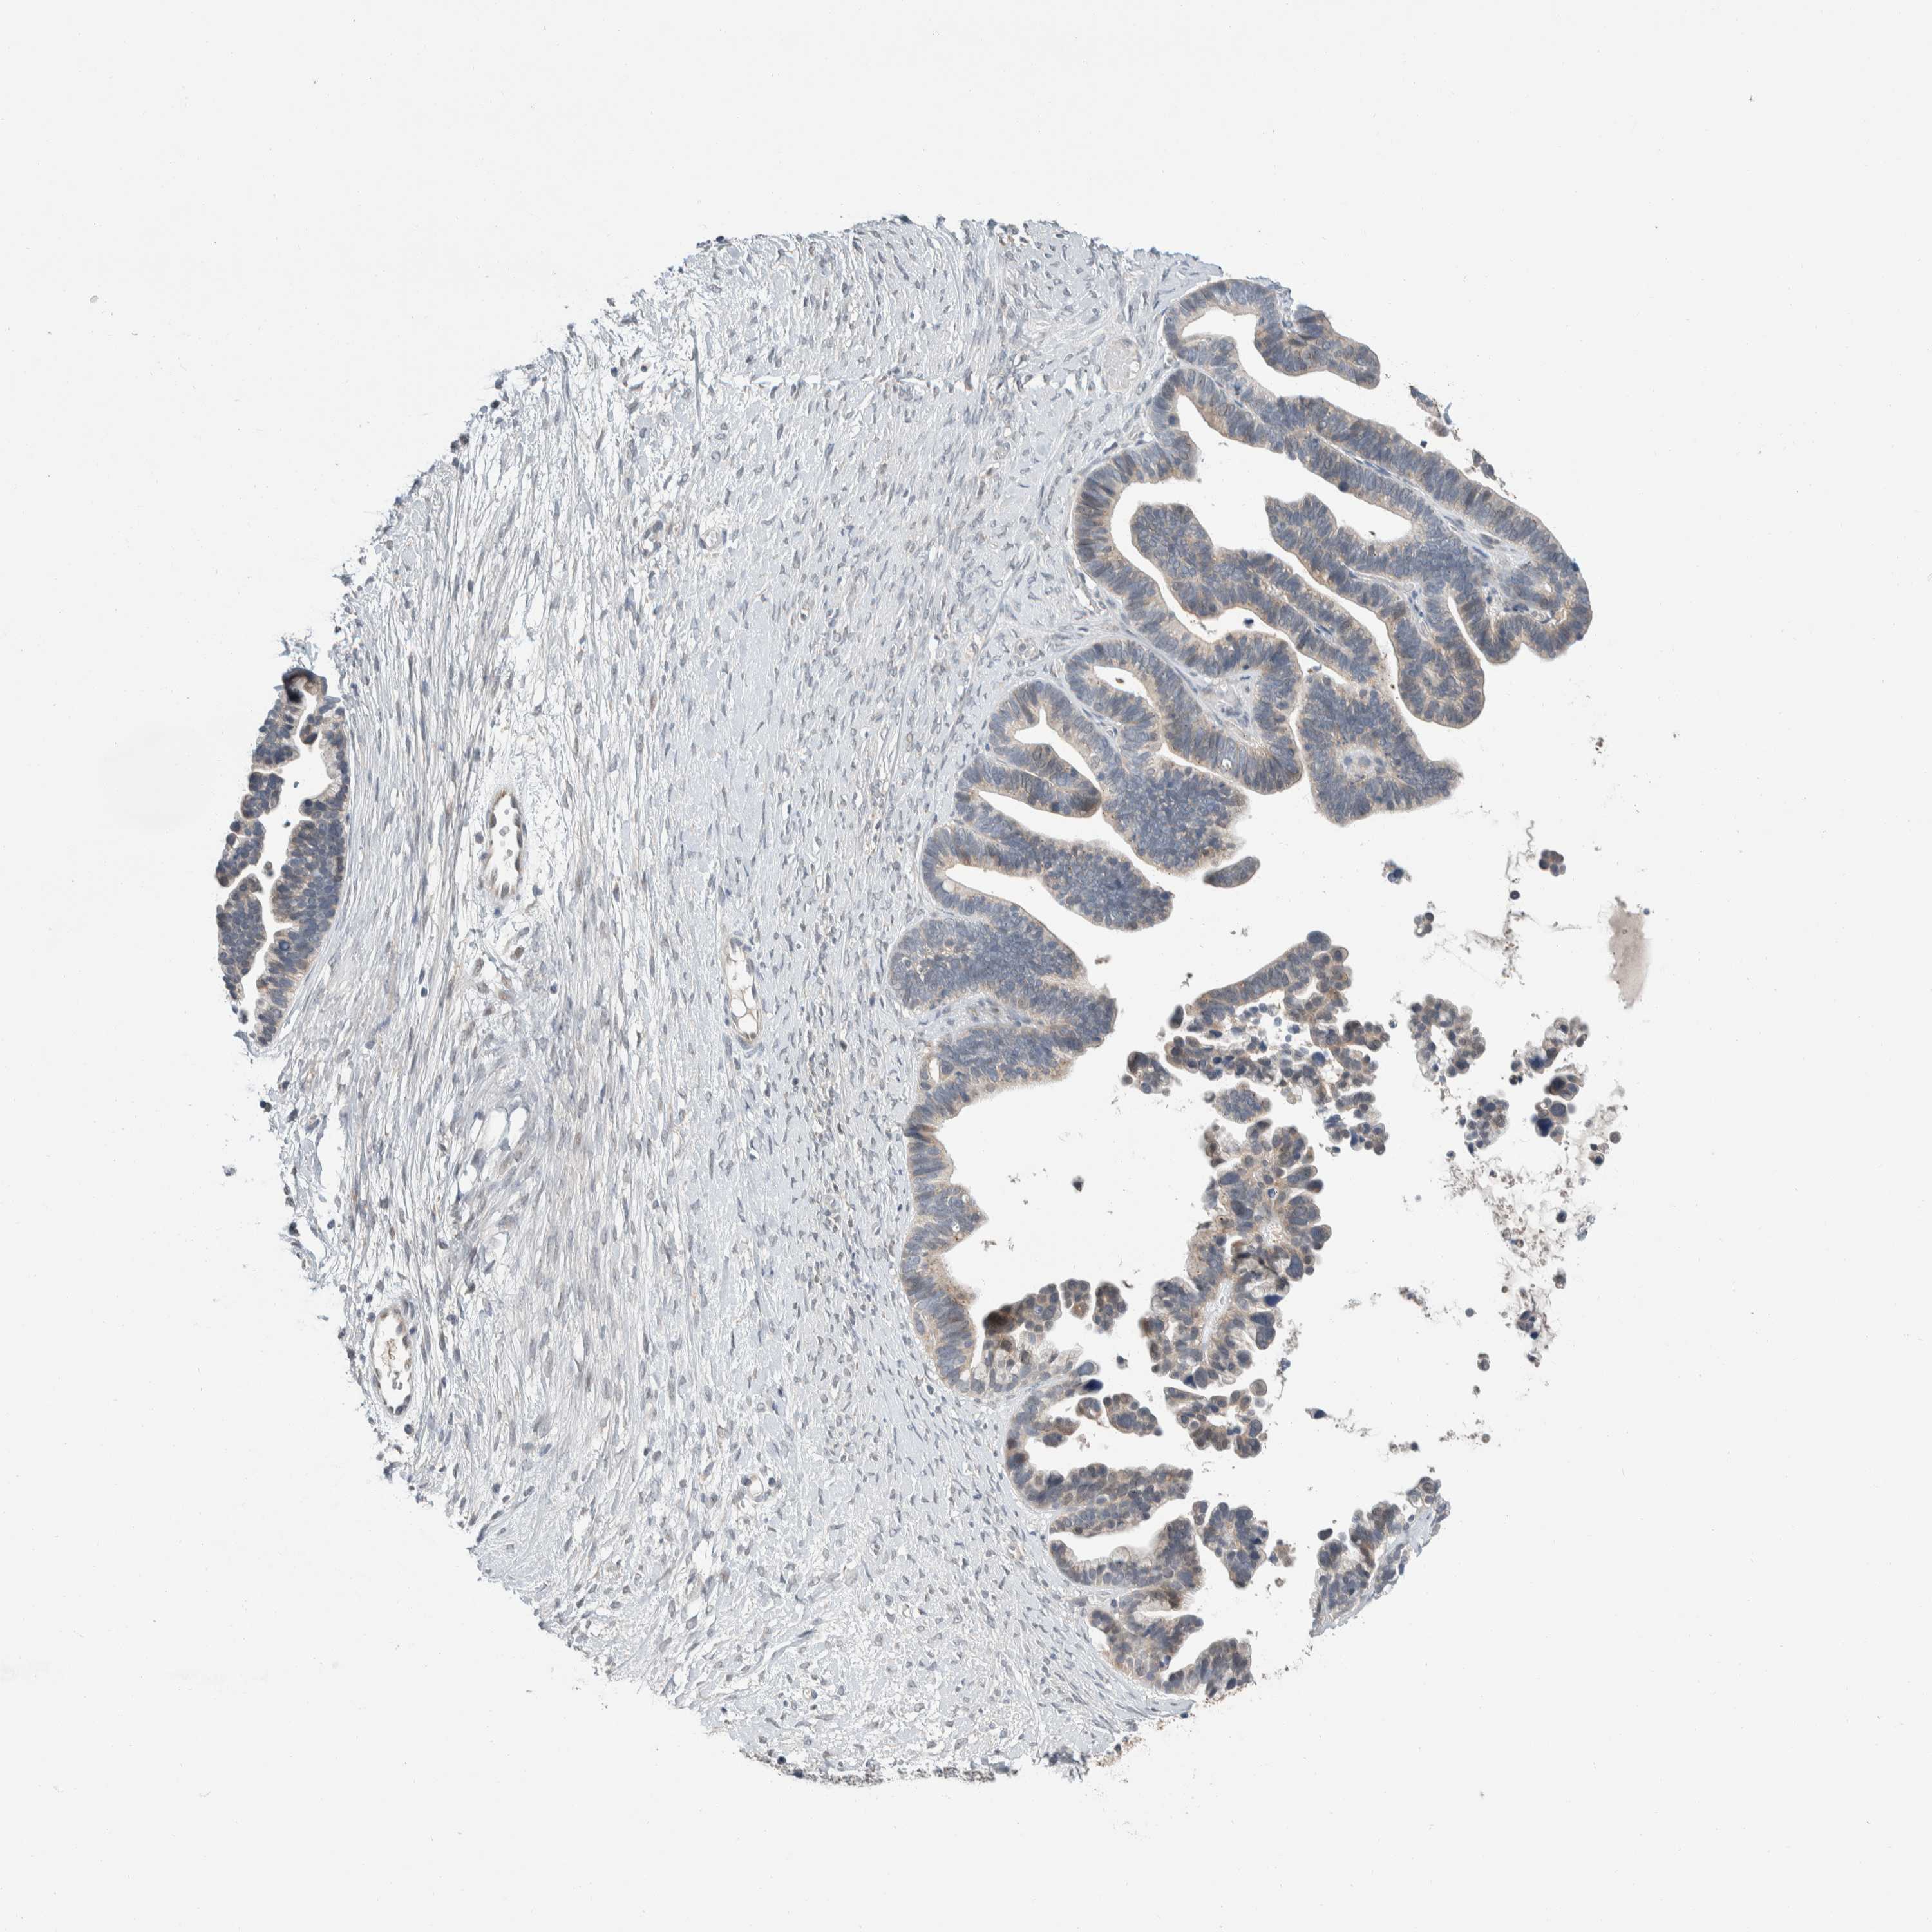

OVARIAN CANCER - Protein expressioni

A mouse-over function shows sample information and annotation data. Click on an image to view it in a full screen mode. Samples can be filtered based on level of antibody staining by selecting one or several of the following categories: high, medium, low and not detected. The assay and annotation is described here.

Note that samples used for immunohistochemistry by the Human Protein Atlas do not correspond to samples in the TCGA dataset.

Antibody stainingi

Antibody staining in the annotated cell types in the current human tissue is reported as not detected, low, medium, or high, based on conventional immunohistochemistry profiling in selected tissues. This score is based on the combination of the staining intensity and fraction of stained cells.

Each image is clickable and will lead to virtual microscopy that enables deeper exploration of all samples and also displays staining intensity scores, fraction scores and subcellular localization as well as patient and tissue information for each sample.

Antibody HPA024361

Antibody HPA064939

Cystadenocarcinoma, serous, NOS

Carcinoma, endometroid

Cystadenocarcinoma, mucinous, NOS

Carcinoma, NOS